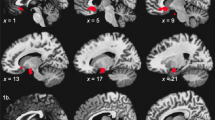

There is continued misunderstanding within the imaging field (although it is not relegated solely to imaging studies) about the role of statistical adjustment of accepted type I error rate, the relationships of statistical threshold adjustment to chances for replication, and whether such one-off studies can actually diminish the type I error without negatively compromising a scientific line of inquiry. Statisticians often counsel on the careful selection of a p value to balance out the nature of a false positive, type I error, vs a type II, negative error [36, 67]. In addition, the concept of meaningfulness of a significant effect – does it help us to understand illness, treatment with a reasonable degree of precision and effect size, is often lost in the discussion [64, 68]. We hope to illustrate that the concerns about type I error are valid, but that they have mislead reviewers and the field into a p value war that can only sacrifice type II error, clinical significance - and will very likely reduce the capability of time tested strategies like replication and meta-analysis. Figure 1, Panel A is an actual illustration of the relationship between sample size and statistical significance using GPower. We set alpha at .005, as our experience suggests that this threshold has a balance between statistical stringency and clinical significance. To achieve significance with an alpha of .005 and power of .80, an effect size of 1.25 (very large) is needed with equal samples of 20. This means that many comparison studies are underpowered for large and medium effect sizes, they would have a higher likelihood for non-significance in this scenario (type II error). This is particularly troubling, as the vast majority of medical treatments have small to moderate effect sizes (Fig. 1, Panel B). So, would we counsel throwing away the baby with the bathwater?

A. Illustrates the observed N needed to obtain power of .80 to reject the null hypothesis, in a given voxel, based upon alpha < .005. This is independent of adjustment for cluster size. A exponential fit line is include to illustrate the relationship between sample size and power. B. Effect sizes for comparison with 1B. Most psychotherapies are moderate effect sizes, suggesting that a similar brain effect size would have adequate power with Ns of between 50 and 109. The assumption is that the brain marker would have the same effect size as the treatment. Brain effect sizes may be larger or smaller, as it is doubtful that they are parametrically linked. Effect sizes from Meyer et al., 2001 [69] and Leuck et al., 2013 [70]